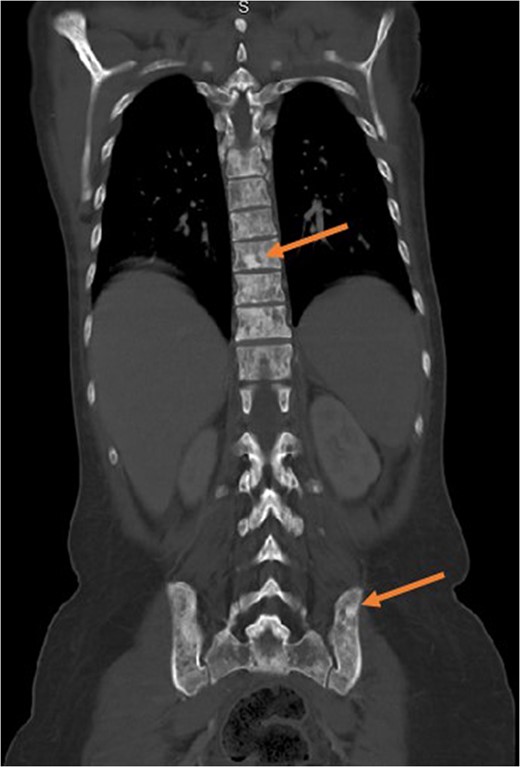

Evaluation of anemia and thrombocytopenia began with exploration of common causes. Mean corpuscular volume was 106 fl, red blood cell distribution width 30%. Manual blood count showed moderate polychromasia with both microcytic and macrocytic red blood cells. Schistocytes were visualized on blood smear. Haptoglobin was low (<15 mg/dl), while reticulocyte count was elevated (12.9%). Total iron and ferritin were both elevated (262 µg/dl and 1032 ng/dl, respectively). Vitamin B12 was elevated while folate was within normal limits. Initial imaging included computed tomography of her chest, abdomen and pelvis, which revealed diffuse skeletal metastases, masses in both breasts, hepatosplenomegaly and mesenteric stranding with trace ascites (Figs 1 and 2).

Computed tomography showing diffuse metastases to the spinal column and pelvis. This image exemplifies the propensity of signet-ring cells for bone and bone marrow, leaving other organs essentially untouched.